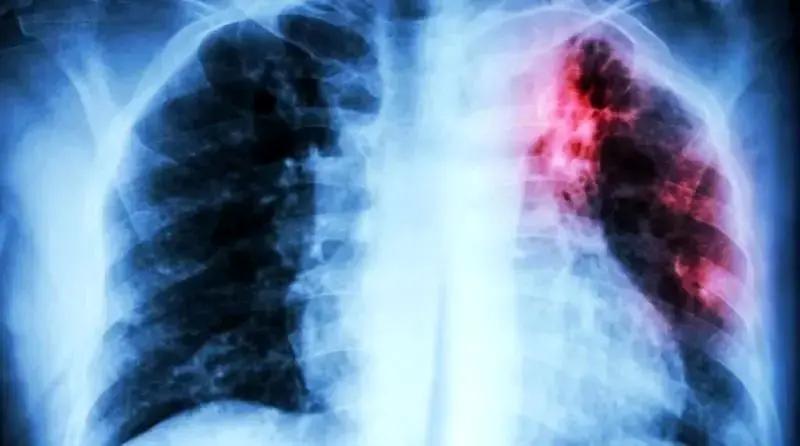

به گزارش رکنا، سازمان بهداشت جهانی (WHO) گزارش داده که بیماری سل (Tuberculosis) همچنان عنوان مرگبارترین بیماری عفونی جهان را حفظ کرده و در سال ۲۰۲۴ موجب مرگ ۱.۲۳ میلیون نفر شده است.

بر اساس آمار ارائهشده در گزارش جهانی سل ۲۰۲۵ ، این بیماری عفونی در سال گذشته همچنان در صدر لیست بیماریهای کشنده قرار داشته است. با این وجود، برای اولین بار پس از دوران همهگیری کووید-۱۹ شاهد کاهش همزمان در موارد ابتلا به سل (حدود ۲ درصد) و همچنین مرگومیر ناشی از این بیماری (۳ درصد) بودهایم. اما سازمان بهداشت جهانی هشدار داده که این موفقیتها پایدار نیستند .